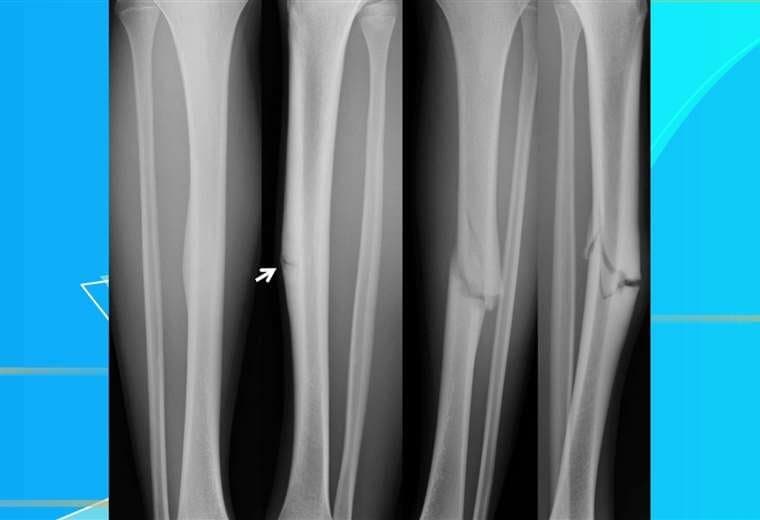

¿Ha escuchado el término fracturas por estrés? Estas lesiones son causadas por la fuerza repetitiva, a menudo por el uso excesivo, como saltar varias veces de un lado a otro o correr largas distancias.

Estas fracturas por sobrecarga también se pueden desarrollar por un hueso debilitado debido a una afección como la osteoporosis.